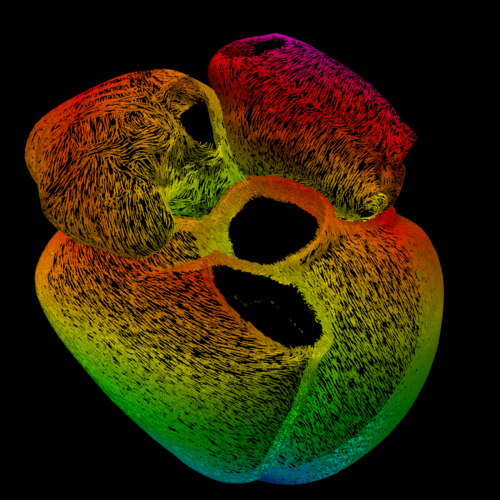

South London doctor wins British Heart Foundation picture competition

A scientist has won the British Heart Foundation’s (BHF) annual Reflections of Research image competition.

The competition challenges BHF-funded scientists to put forward the most awe-inspiring image taken as part of their research into cardiovascular health and disease.

Each offers a stunning insight into their crucial work.

Paths of the Heart wowed the judges and took home the top prize. Entered by BHF-funded researcher Dr Marina Strocchi, it was taken as part of her work at King’s College London’s department of Biomedical Engineering, based at St Thomas’ Hospital in Westminster Bridge Road, Lambeth.

The multicoloured structure, generated by a computer model, is a map of bundles of cells that together make up the heart muscle.

These bundles, each shown by a separate line, transmit the electrical signal that causes the heart to beat. The direction each line is pointing indicates the direction the electrical signal travels.

The signal starts in the two top chambers of the heart, the atria, and moves to the bottom two, the ventricles.

By accurately modelling the heartbeat signal as it passes through the heart, Dr Strocchi can simulate how an individual patient’s heart works, to better predict how they will respond to different treatments.

The doctor said: “I am thrilled that my entry was chosen by the judges as this year’s winner. It is great to be able to share the beautiful side of my research.

“In our research, computer models help doctors understand so much more about diseases of the heart.

“By simulating how electrical activity spreads through the heart, following the direction shown in the picture, to then trigger a heartbeat, we can predict how specific patients will respond to treatments to personalise and adjust how we care for them.”

Pictured top: The winning submission, Paths of the Heart Dr Marina Strocchi (Picture: BHF/Marina Strocchi)